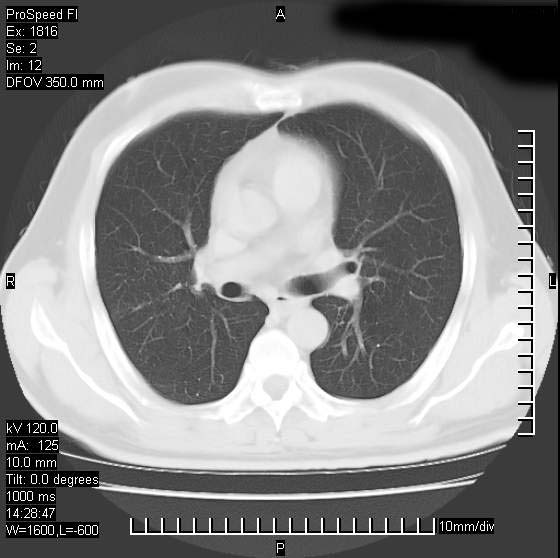

男性,50 ,肺结核9年,咳嗽,胸痛一周。右上肺见一厚壁空洞,周边有点样钙化,胸膜牵拉,洞壁较光整。诊断结核性空洞。有癌性的可能吗? 余肺野无异常,没有上传。

洞壁较厚内壁比较光整,两个病灶有关联性,纵隔淋巴结不大,考虑结核性空洞。

部分层面见空洞为近似新月形,洞壁内缘尚规整且近肺门侧,周围见索条影、卫星灶,结合病史,首先考虑肺tb可能大。

右肺上叶为两个病灶,前面为陈旧型结核灶,其后方病灶像肺脓肿